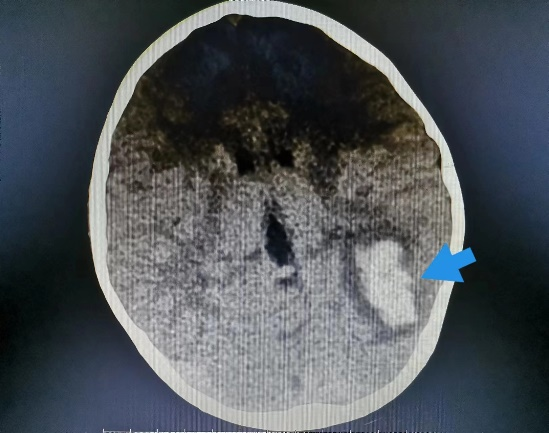

近日,一向身体健康的8岁的小男孩小阳(化名),几天前突然开始剧烈头痛,反复恶心、呕吐,奶奶赶紧把他送到我院就诊。 起初,大家认为小阳只是简单的感冒或则肠胃问题,普通检查没有找到病因,最终在颅脑CT提示下发现小阳“左侧枕叶脑出血伴血肿形成”。 患儿入院影像(左图为颅内出血、右图为胸腔积液及心包积液) 入住神经外科后,考虑到小阳近期并没有受过外伤,依据既往经验,小阳的脑出血可能是先天性血管畸形,但完善相关脑血管检查后却提示小孩脑血管正常,诊断一时陷入了僵局。 仔细问诊 查找蛛丝马迹 经过不断询问,副主任医师汪棋笙了解到小阳来自山区农村,且平时有喝生水和吃生螃蟹的习惯,汪棋笙似乎找到了诊断的关键。回顾了小阳血常规结果嗜酸性粒细胞较正常增高4倍,结合患儿心肺CT提示心包积液、胸腔积液,存在多器官损害表现,汪棋笙高度怀疑小阳就是肺吸虫感染、脑型肺吸虫病。 多方打探 从成都邀请工作人员上门检测 近年来肺吸虫病感染率非常低,肺吸虫血清抗体检测在周边各大医疗中心均已停止开展此项检查,诊断再次陷入困难。经多方打听,最终联系到可以开展此项检测的机构,为此,科室立即联系,邀请工作人员从成都赶来上门抽血检测。最终确立了肺吸虫感染、脑型肺吸虫病的诊断。 寻遍全省 获得特效药 尽管小阳的诊断已明确,可新的问题又再次出现,治疗肺吸虫的特效药物“吡喹酮片”医院及市场上已经无法购得。科室可谓是全员出动,寻遍各级医疗机构,最终从四川省疾控中心获得该药物,治愈了小阳。 患儿出院影像(颅内出血、胸腔积液及心包积液已基本吸收) 特别提醒: 饮用生水或吃了未经煮熟的青蛙、蛇等肉类,容易导致寄生虫感染,寄生虫可进入血管,并通过血液循环进入大脑内生存,引发相关脑病。 肺吸虫是什么? 肺吸虫又称并殖吸虫,是甲壳类哺乳动物的常见人兽共患寄生虫。当它们在组织中迁移时会引发嗜酸性反应,因此我们可以在化验单上看到嗜酸性粒细胞增多。肺吸虫感染人体后主要寄生于肺部,还可异位至脑部、腹部及皮下等部位,引起相应的器官组织病变。 哪些习惯容易招虫? 近年来发病率有所下降,但在部分人或因饮生水、生食或者半生食虾蟹的习惯,导致该病时有发生。 如何预防肺吸虫感染? 1.不要随意喝生水,尤其是河水、小溪水等。 2.切勿吃生的淡水螃蟹、小龙虾等,一定要煮熟。 3.避免食用未煮熟的其它淡水甲壳类动物或来自污染水源的淡水鱼类。 神经外科联系电话:0830-5216264